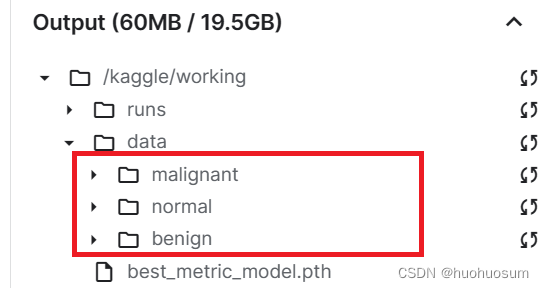

(1)在kaggle建立数据目录

source_dir = r'/kaggle/input/breast-ultrasound-images-dataset/Dataset_BUSI_with_GT'

target_dir = r'/kaggle/working/data'

import shutil # 删除工作目录,避免后续操作错误

if os.path.exists(target_dir):

shutil.rmtree(target_dir)

# 建立目录

# 列表表达式,获得source_dir目录下的所有数据目录,即类别列表

class_names = sorted(x for x in os.listdir(source_dir) if os.path.isdir(os.path.join(source_dir, x)))

for i in range(len(class_names)): # 在target目录下新建类别目录

if not os.path.exists(os.path.join(target_dir,class_names[i])):

os.makedirs(os.path.join(target_dir,class_names[i]))

新建目录结果如下图所示: